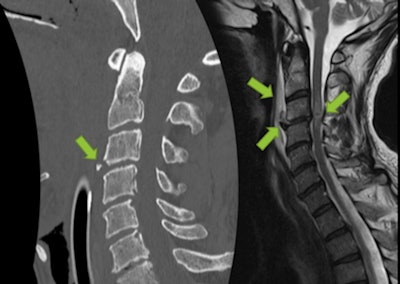

Even in the absence of skull or cervical fractures, patients may present with vascular injuries, so a high degree of suspicion is required from the examiner. Mechanisms of hyperflexion, hyperextension, acceleration, or deceleration should raise a red flag and elicit a more comprehensive investigation. In the acute setting, CT angiography is preferred over MR angiography if the patient presents with one of these mechanisms and/or skull base fractures and/or cervical fractures involving the vertebral foramina.

CT of the spine highlights fractures and dislocations, raising suspicion of ligament and spinal cord injuries, but MRI has superior sensitivity for these injuries and can confirm soft tissue lesions, vertebral canal hemorrhages, and spinal cord injuries.

Falls after a jump result in the highest rate of thoracic and lumbar fractures in skiers (56% and 31%, respectively) and snowboarders (50% and 50%, respectively). Thoracolumbar fractures generally are associated with a lower incidence of neurological deficit, and most of them are simple compression fractures. The fall after jump mechanism results in the lower occurrence of neurological injury. Conversely, skier-versus-skier collisions result in the highest incidence of cervical injuries in skiers (50%) and snowboarders (80%), which are the injuries more often associated with neurological deficits, Dalaqua and colleagues concluded.